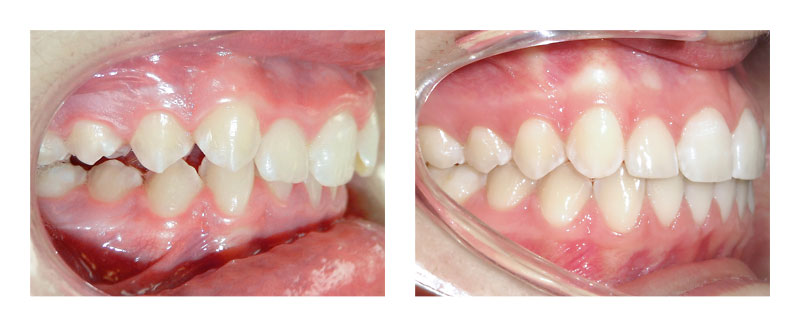

Cas Orthodontie Paris 3 : Recul de dents supérieures sur minivis

Les dents du fond (prémolaires et molaires) à l'arcade supérieure se sont avancées, privant les canines supérieures de place (évolution en double rangée). L'avancée de ces dents postérieures a aussi créé un décalage entre les arcades dentaires d'une dent (7mm).

Ce traitement de 2 ans a consisté à reculer sur minivis les dents du fond supérieures pour récréer la place pour les canines et corriger le décalage d'avant en arrière. Le traitement a aussi permis de libérer la croissance de la mâchoire inférieure, ce qui a amélioré le profil de la patiente par avancée du menton. Il est à noter que la finesse des gencives au niveau des dents antérieures supérieures interdisait une avancée trop importante des incisives supérieures sous peine d’avoir des récessions gingivales.